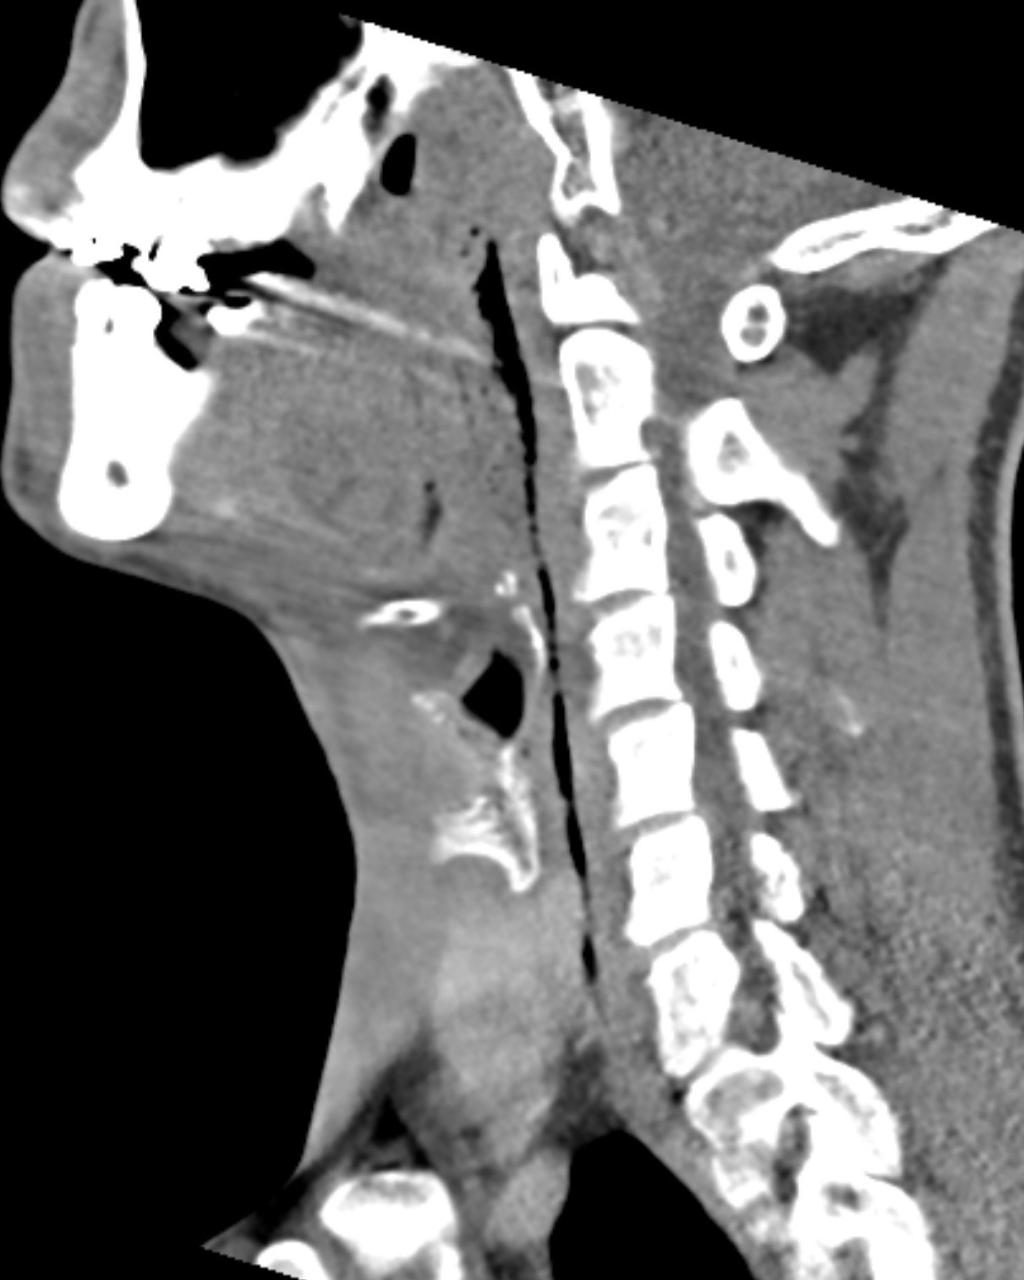

Een man komt op de SEH met een wond aan de hals die hij de avond daarvoor had opgelopen bij een val in de bosjes. De wond wordt steeds pijnlijker. Over een traject van 5 mm is de bodem van de wond niet te zien. Er is minimale zwelling en er zijn geen crepitaties te voelen. De diagnose wordt gesteld op de CT-scan.

Wat is de diagnose?